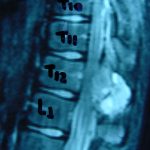

Εικ. 3: Μαγνητική τομογραφία α-στ Οβελιαία (Saggital) λήψη ακολουθία Τ1-Τ2, ζ-ιβ Εγκάρσια (Axial) λήψη ακολουθία Τ1-Τ2

Παρατηρείται ευμεγέθης εξεργασία στα οπίσθια στοιχεία του Θ12 σπονδύλου η οποία προκαλεί διόγκωση των δομών , λέπτυνση του φλοιού, χωρίς σημάδια διάσπασης του φλοιού. Η εξεργασία προβάλλει και στενεύει το σπονδυλικό σωλήνα, ενώ προκαλεί πίεση του νωτιαίου μυελού. Δεν αναγνωρίστηκαν παθολογικά ευρήματα από τον έλεγχο των σπονδυλικών σωμάτων και των μεσοσπονδύλιων τμημάτων της ΟΜΣΣ.